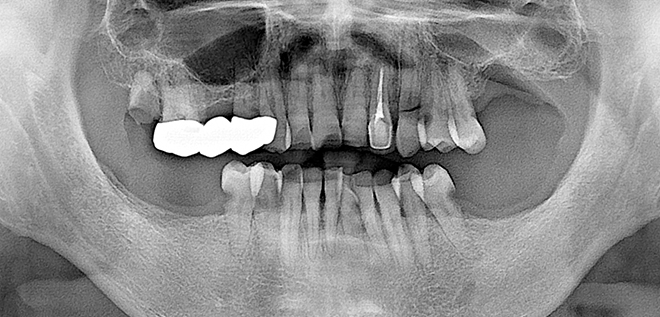

Before & After

어려운 임플란트 시술도

남양바른탑에서는 가능합니다.